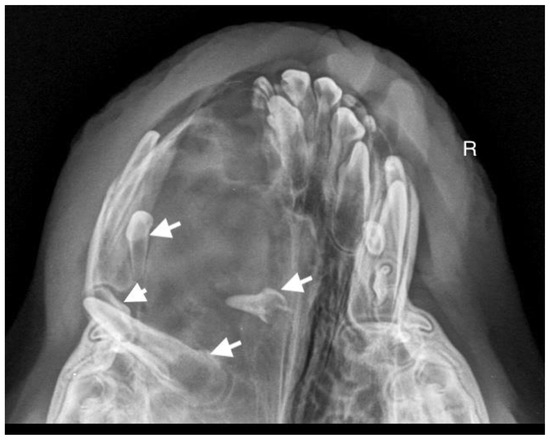

A 10-month-old American Staffordshire Terrier dog was referred for an orthodontic consultation due to abnormal alignment of the maxillary teeth and the resulting bite injuries. Clinical examination revealed three properly aligned incisors on the right side and four incisors (including one tooth with a double crown) on the left side arranged chaotically (Figure 7). Intraoral examination revealed an abnormal palatal crease in the projection of teeth 103–203 and a hard and painful protrusion about 3 cm in diameter on the left side. The roentgenogram showed the presence of three additional incisors, including two unerupted ones, growing in the opposite direction to the alveolar process. The double tooth on the X-ray appeared to be a fused tooth (tooth fusion occurs as a result of physical force or pressure on an adjacent tooth’s bud, leading to the contact of the two tooth buds and their fusion before calcification) [12]. The abnormal growth of the incisors on the left side caused pressure on the incisal bone, along with skewing of the nasal septum to the right side (Figure 8). The third incisor, along with an additional third incisor, showed radiographic features of a dentigerous cyst. A decision was made to perform open extraction of the ectopic teeth using the CLP method.

The bone cavity, after such a large open extraction, was 3.0 cm × 4.2 cm; so, the decision was made to implant polymeric hydroxyapatite with curdlan soaked in 0.9% NaCl into the areas of bone loss. The flap was sutured with 4-0 monofilament single sutures. A follow-up radiograph was taken 28 days after surgery. On clinical examination, the soft tissues were healed properly. On the follow-up radiograph, the bone tissue was healed properly, with new bone formation.

Figure 7. On the left side, the teeth with abnormal eruption are marked with arrows on the X-ray. The right radiograph shows the status 28 days after surgery. Properly formed bone tissue can be seen, with no signs of inflammation or alveolar bone atrophy (marked with arrows).